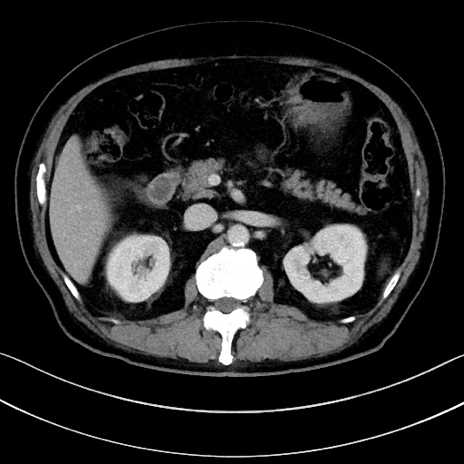

症例15(横断像)

【症例】70歳代男性

【主訴】腹痛

【現病歴】今朝から腹痛あり。全体的に痛い。特に左上の方。排ガスが今日はない。冷や汗が出る。

【既往歴】直腸癌術後

【身体所見】左側腹部〜上腹部に圧痛あり。腹膜刺激症状明らかなではない。軽度反跳痛。左下腹部に術後瘢痕あり。

【データ】WBC 7700、CRP 0.02